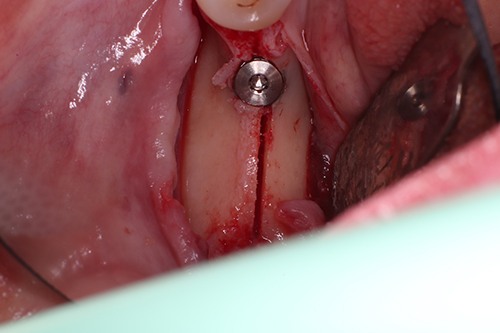

Extraction, Lateral Wall Sinus with Perforation Repair and 2 Immediate Implants